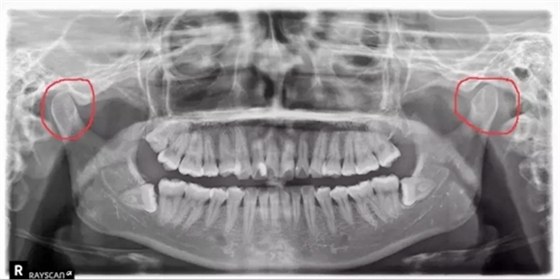

牙科醫(yī)生在看患者的X光片的時(shí)候,經(jīng)常能看出來有的人有偏側(cè)咀嚼的習(xí)慣,導(dǎo)致關(guān)節(jié)一側(cè)大一側(cè)小。

(如下圖:)